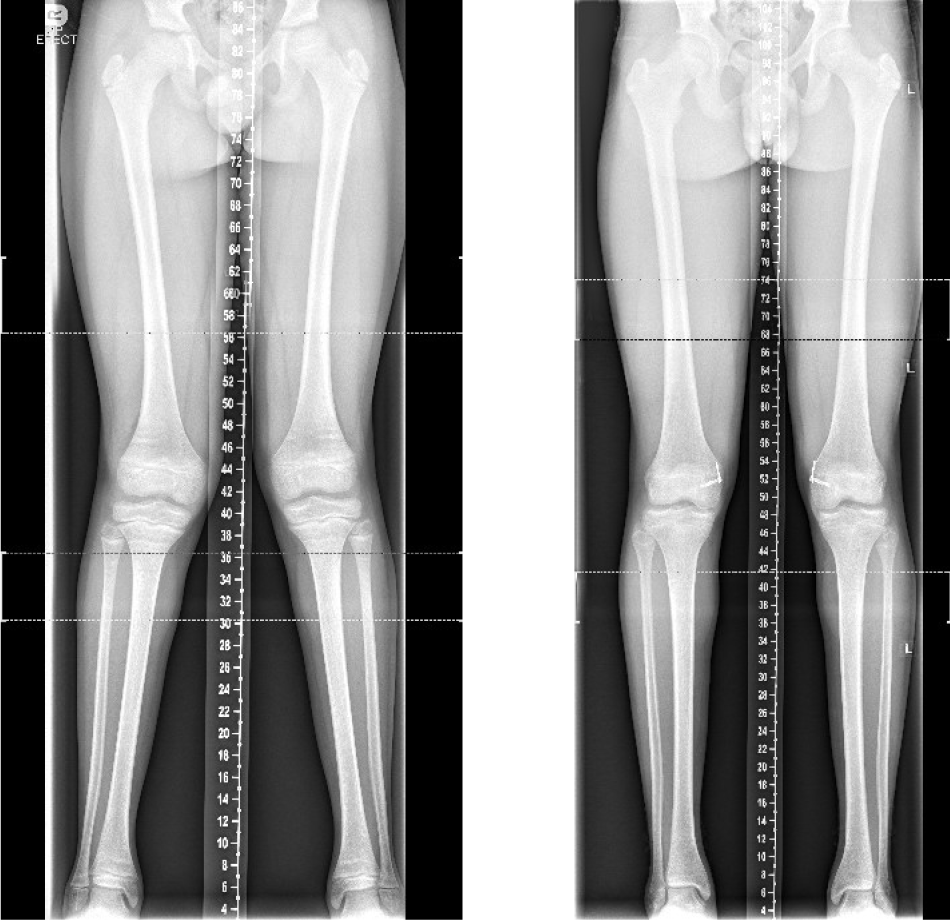

This surgery is often performed when one leg is shorter than the other, to stop the growth of the longer leg, allowing the other leg to catch up over time and ‘even up’ the legs. Epiphysiodesis may also be used to correct an angular deformity of the leg; for example, knock knees. The timing of each procedure is crucial and is calculated to allow the shorter leg to catch up by the time your child’s growth stops.

Your child will be seen regularly in the clinic to check leg length difference or the bend in the legs with x-rays. If eight-plates or screws have been used and your child is still growing, they will need to have another operation to remove them under a general anaesthetic. If an x-ray shows that there is no more growth left, then the plates can remain in.